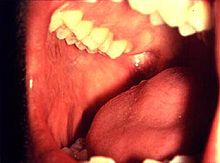

Als Schleimhaut, in der medizinischen Nomenklatur Tunica mucosa (von lat. tunica „Haut, Gewebe(schicht)“ und mucus, „Schleim“) oder kurz Mukosa genannt, wird die Schutzschicht bezeichnet, die das Innere von Hohlorganen auskleidet. Schleimhäute befinden sich in der Mundhöhle und in der Nasenhöhle. Auch die Bindehaut des Auges, die Wandungen der Vagina, die Deckschicht der Eichel der KlitorisEichel des Penis sowie die Innenseite der Penisvorhaut sind Schleimhäute. Im Gegensatz zur äußerlichen Haut besitzt die Schleimhaut keine Hornschicht und keine Haare. Wesentlich (und namensgebend) für Schleimhäute ist die Produktion von Schleimstoffen, den Mucinen.

- Mundschleimhaut